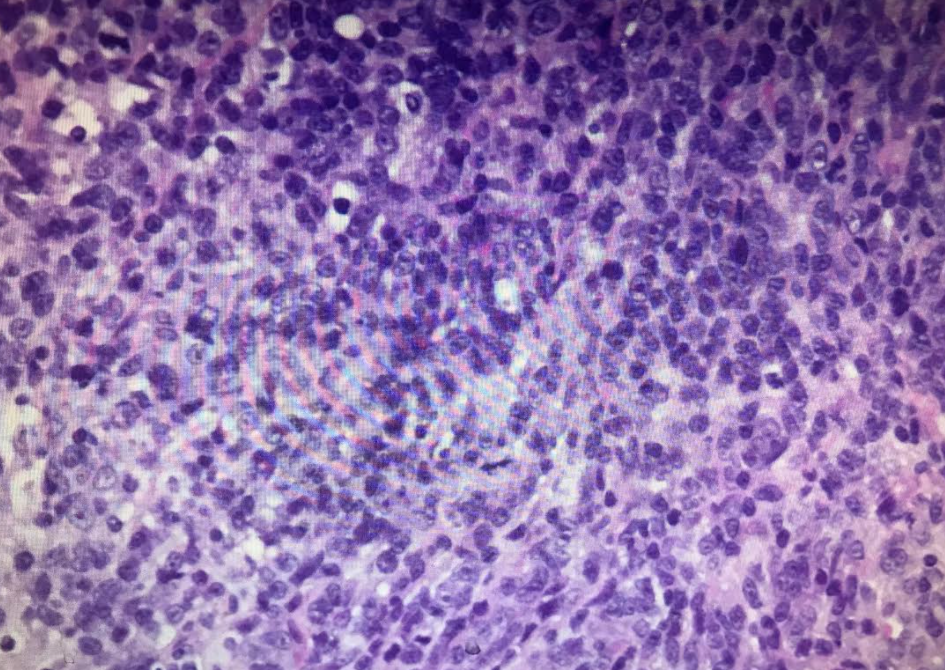

腎臟病理切片下發現淋巴球浸潤